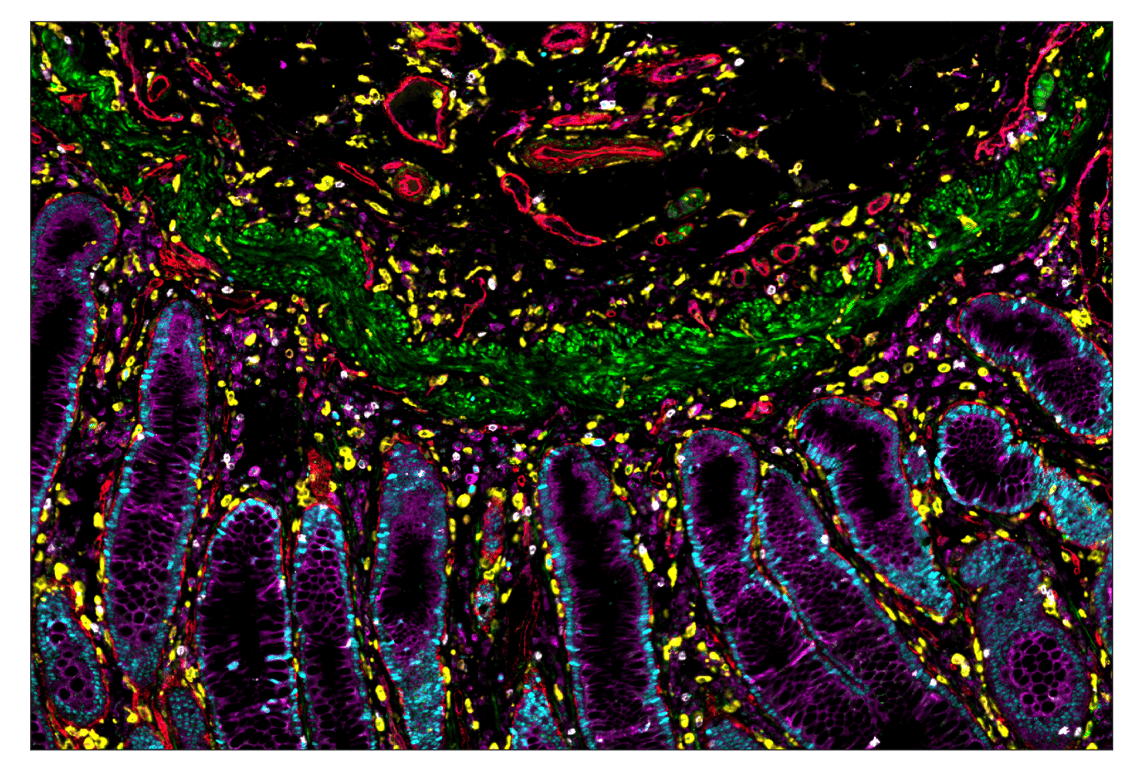

SignalStar™ multiplex immunohistochemical analysis of paraffin-embedded human colorectal adenocarcinoma using OX40L (D6K7R) & CO-0087-488 SignalStar™ Oligo-Antibody Pair #49516 (green), CD14 (D7A2T) & CO-0085-594 SignalStar™ Oligo-Antibody Pair #74041 (yellow), PCNA (D3H8P) & CO-0090-647 SignalStar™ Oligo-Antibody Pair #60626 (cyan), MHC Class I (EMR8-5) & CO-0082-750 SignalStar™ Oligo-Antibody Pair #55370 (magenta), CD141/Thrombomodulin (E7Y9P) & CO-0088-488 SignalStar™ Oligo-Antibody Pair #82890 (red), and CD8α (D4W2Z) & CO-0040-647 SignalStar™ Oligo-Antibody Pair #57623 (white). All fluorophores have been assigned a pseudocolor, as indicated. Staining was performed on the BOND RX autostainer by Leica Biosystems.

Immunohistochemistry Image 7: OX40L (D6K7R) & CO-0087-488 SignalStar<sup>™</sup> Oligo-Antibody Pair